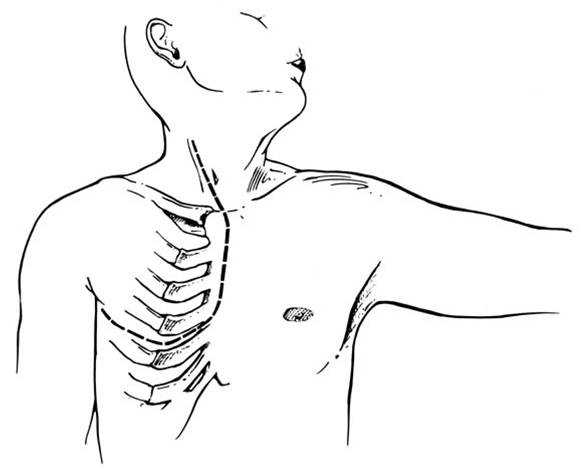

Hemiclamshell Thoracotomy with neck extension

If a large tumor extends into the neck area, an extension along the anterior border of the sternocleidomastoid provides excellent exposure, especially if dissection of the vascular structures is required. This provides excellent exposure of the carotid and jugular vessels (Figures 6, 7).